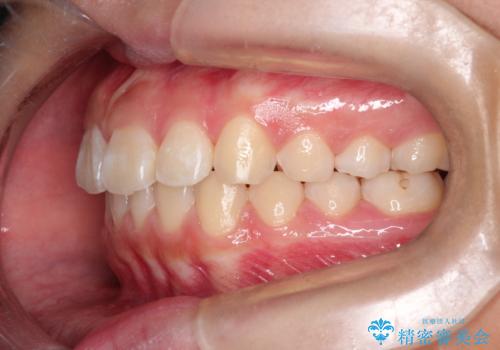

- 前歯が出ているのを主訴に来院されました。

上の前歯が前方に傾斜しており、上の前歯と下の前歯が接触していない状態でした。

上の奥歯を後方に移動させて、前歯を引っ込める計画としました。

しっかり使っていただけたので、スムーズに治療を終了することができました。